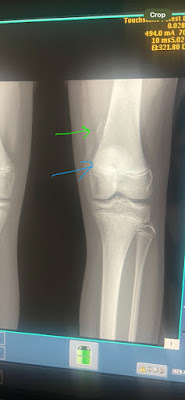

While Caden was away at basketball camp, Annabelle had a serious of appointments and scans for a lump she discovered a few weeks ago. After a sonogram, x-ray, and MRI, she was diagnosed as having an osteochondroma. It's basically a broccoli floret piece of bone on her femer...some cells gone rogue. Doctor said it's likely been there for a few years, and it is just now to the size that she noticed it. It will keep growing as long as she is growing, so we will monitor it and hope surgery isn't needed. You can see it (green arrow), and then you can see (blue arrow) that her growth plates are still open.